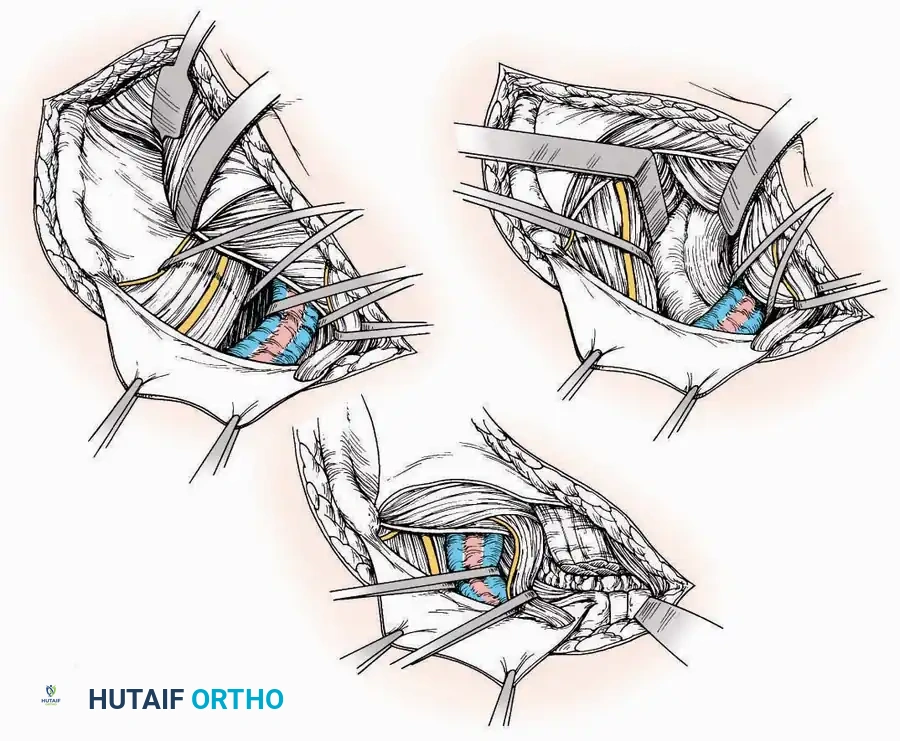

Medial Approach

Indications: Fixation of sustentaculum tali fractures, medial process fractures, or excision of medial tarsal coalitions.

Positioning: Supine with the hip externally rotated and knee flexed (figure-of-four position).

Surgical Technique:

* Incision: Begin 2.5 cm anterior and 4 cm inferior to the medial malleolus. Carry it posteriorly along the medial surface of the foot toward the Achilles tendon.

* Superficial Dissection: Divide the fat and fascia to define the inferior margin of the abductor hallucis muscle.

* Deep Dissection: Mobilize the abductor hallucis muscle belly and retract it dorsally to expose the medial and inferomedial aspects of the calcaneal body.

* Plantar Exposure: Continue distally by dividing the plantar aponeurosis and the muscular attachments to the calcaneus, or strip them subperiosteally with an osteotome.

* Neurovascular Warning: Meticulously identify and protect the medial calcaneal nerve and the nerve to the abductor digiti minimi (first branch of the lateral plantar nerve), which are highly vulnerable during inferior retraction.